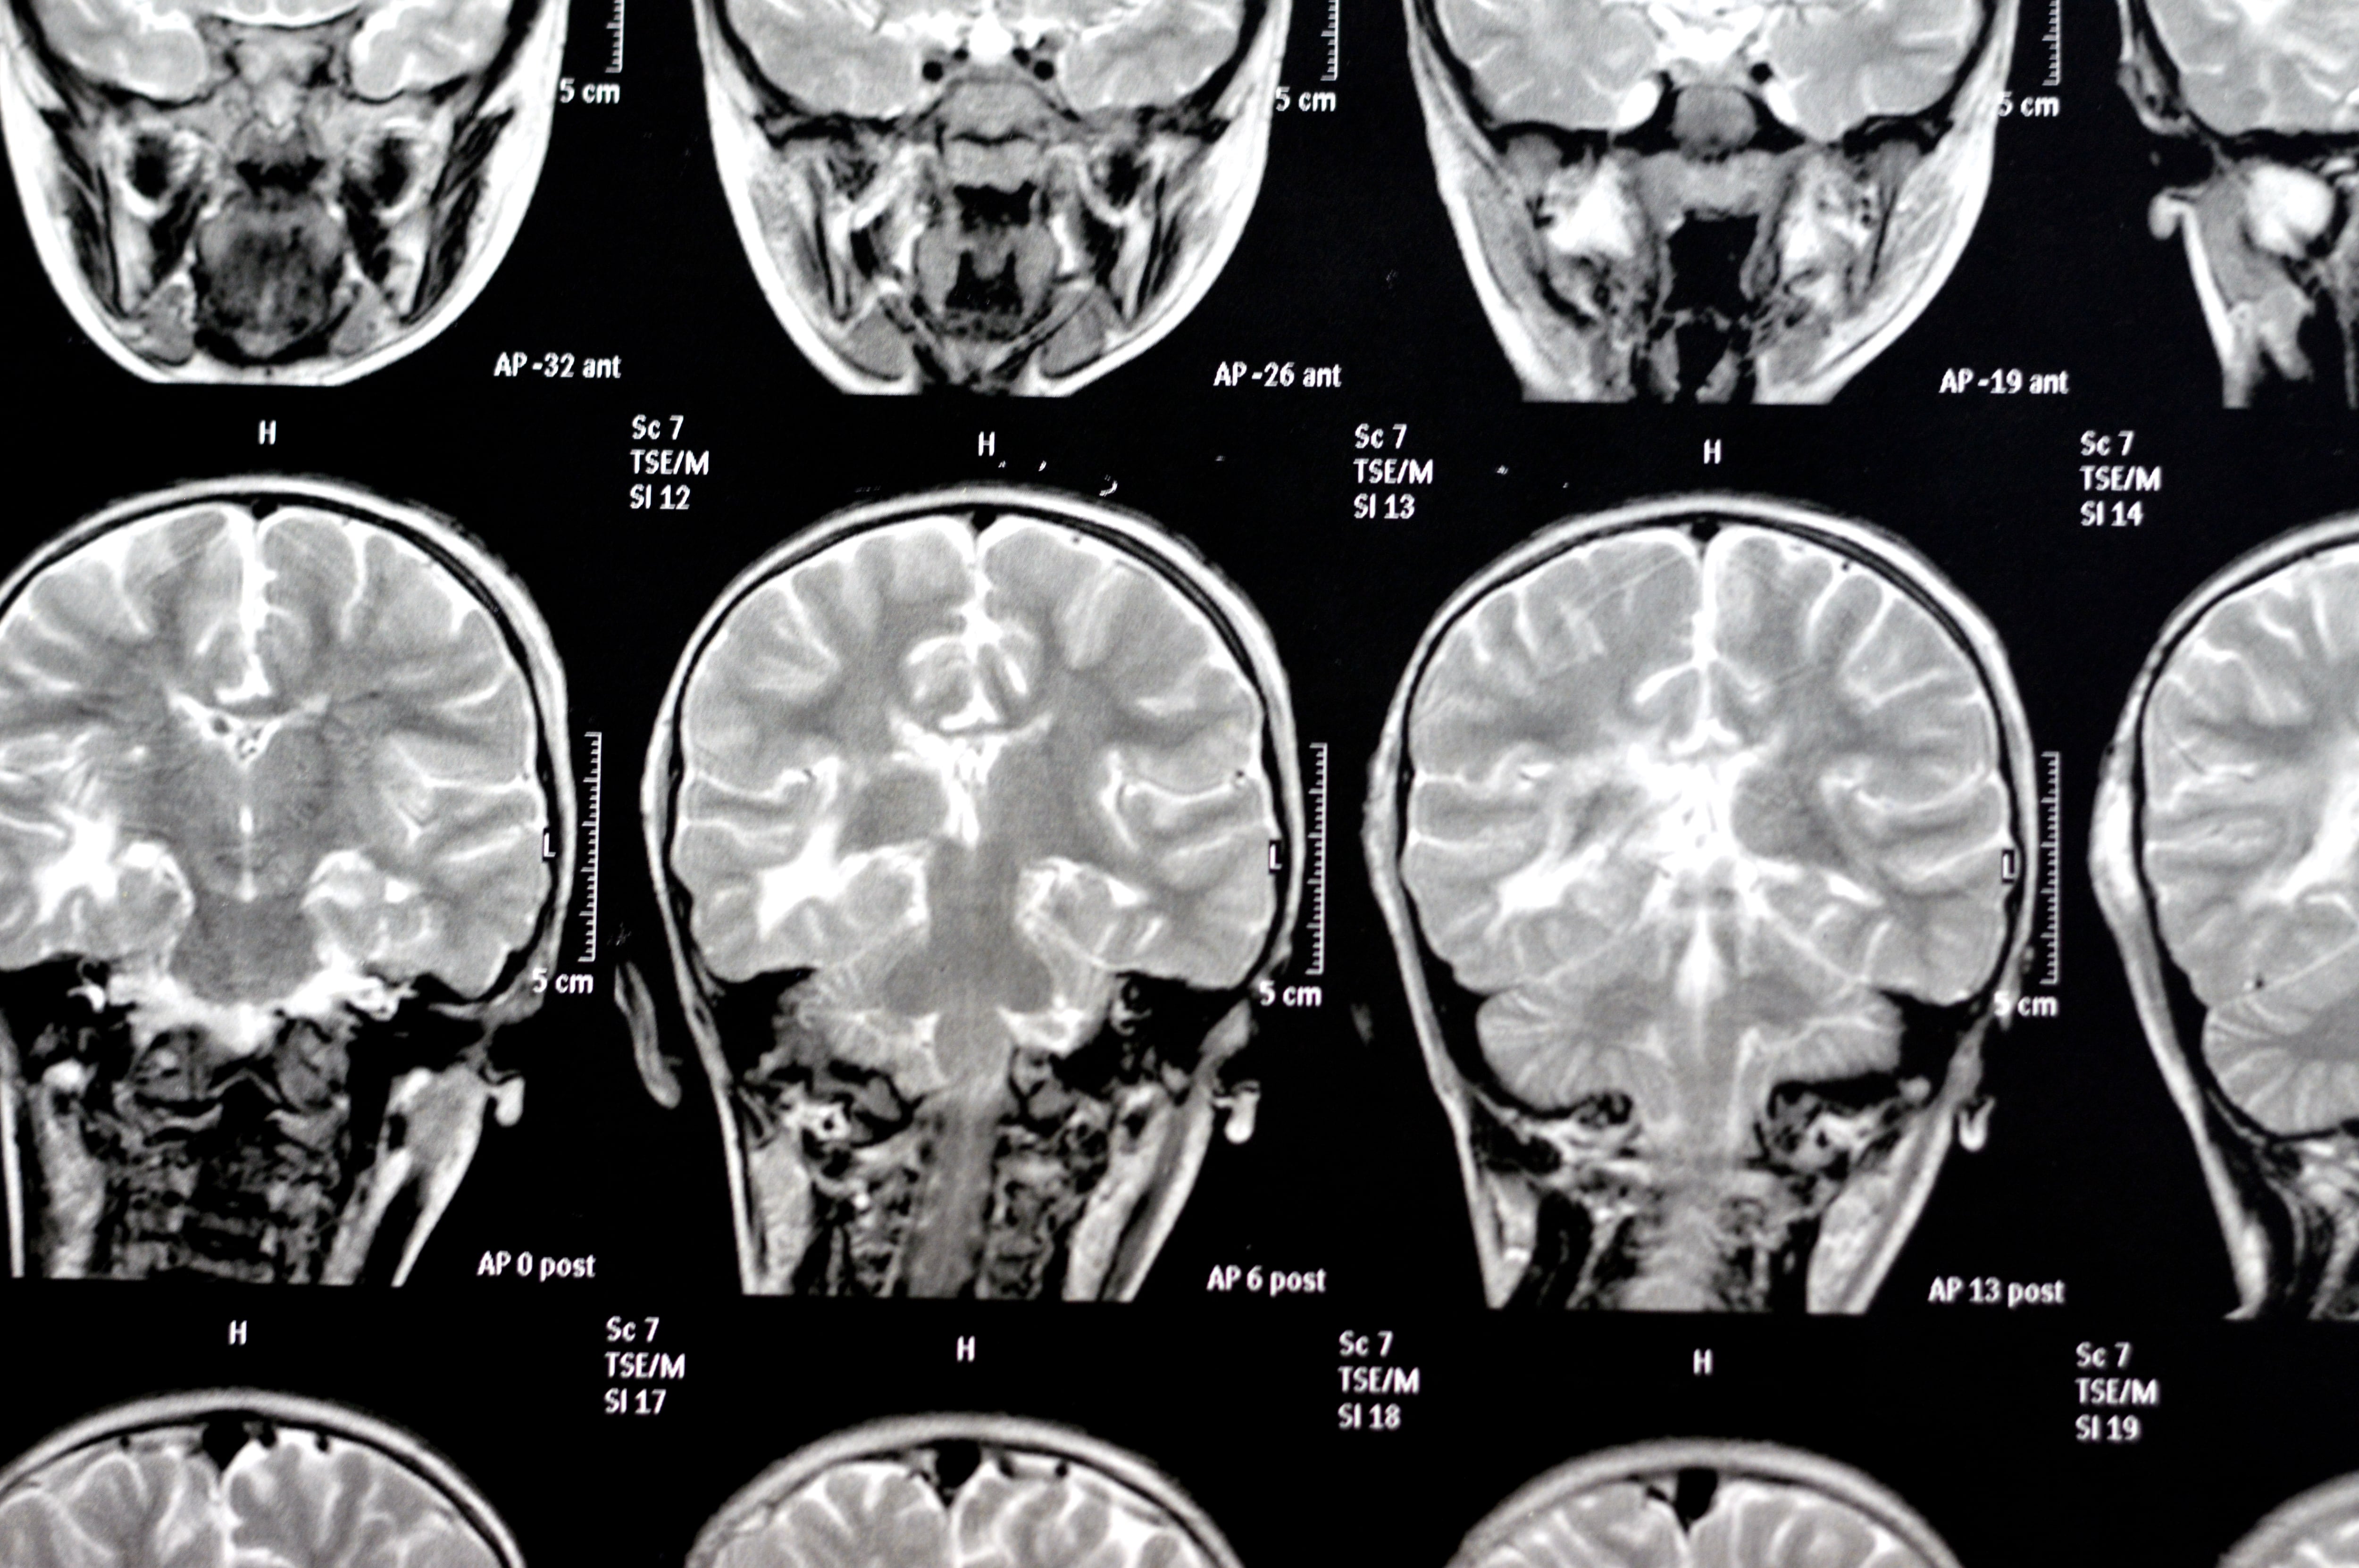

De Borges a Jennifer Aniston: la ciencia empieza a iluminar los misterios de la memoria

¿Cómo afectan los móviles a nuestros recuerdos? ¿Qué porcentaje tienen estos de imaginación? Un grupo de neurocientíficos intenta desentrañar los secretos de una de las funciones más cotidianas y desconocidas del cerebro